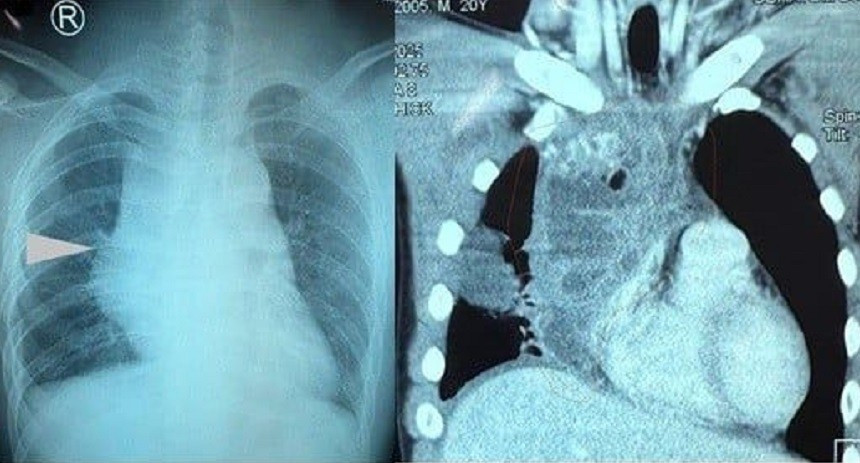

Người bệnh là nam sinh viên N.T.V. (20 tuổi) trước đó hoàn toàn khỏe mạnh, chơi được nhiều môn thể thao như đá bóng, cầu lông, bơi lội. Cách thời điểm nhập viện khoảng hai tuần, anh xuất hiện đau lưng vùng xương vai phải, lan ra trước ngực, cảm giác căng tức và khó thở tăng dần. Khi đến Bệnh viện Nhân dân 115 kiểm tra, hình ảnh X-quang ngực cho thấy bóng trung thất to bất thường.

Ngày 12/10, thông tin từ bệnh viện cho biết, qua chụp CT ngực có cản quang, các bác sĩ phát hiện khối u rất lớn trong trung thất, kích thước khoảng 10 x 7 x 7cm. Khối u chèn ép mạnh vào tim, phổi và tĩnh mạch chủ, gây tụ dịch quanh nhĩ phải và xẹp thùy dưới phổi phải.